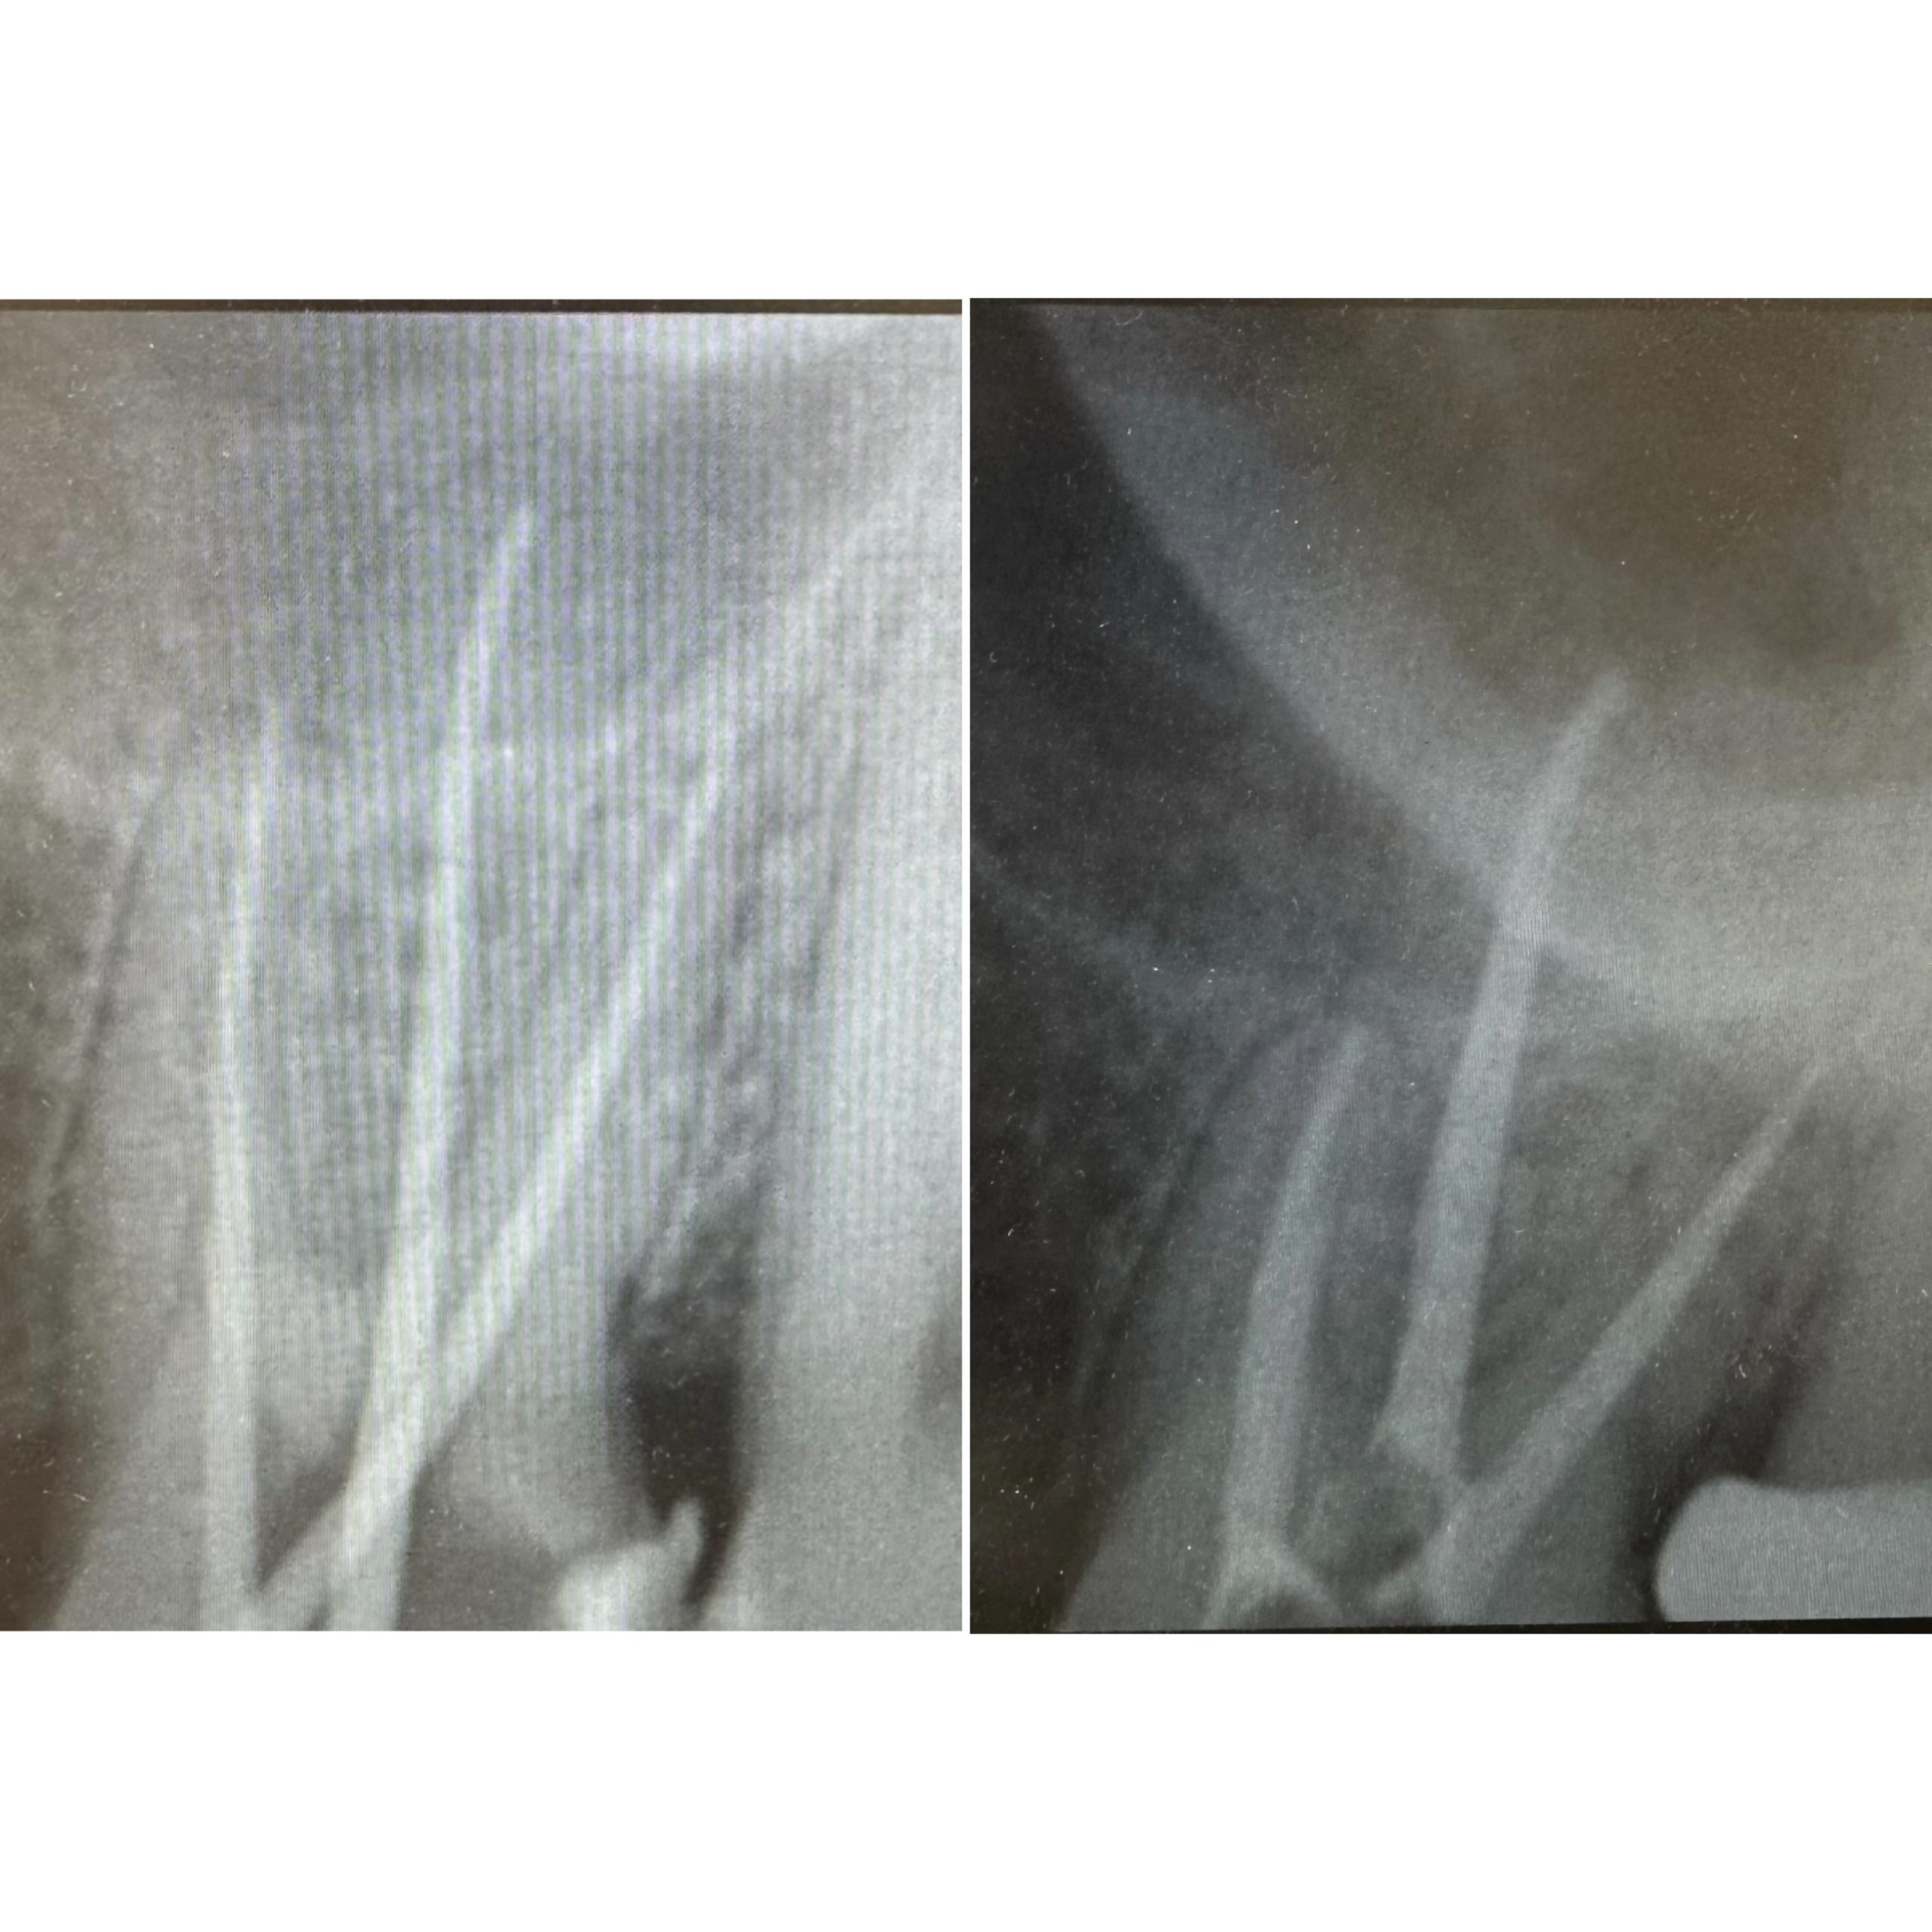

• Диагностика и лечение кариеса и его осложнений (пульпиты, периодонтиты)

• Эндодонтическое лечение корневых каналов с использованием стоматологического микроскопа